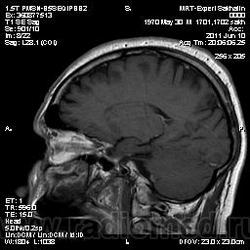

Мужчина обратился к нам без направления.Жалобы на головную боль( он не совсем русский, поэтому плохо понимал вопросы, соответственно и не знал, как на них ответить)- в общем жалобы смутные и непонятные.

Провели исследование.Что скажете, уважаемые коллеги

Выраженное утолщение слизистой оболочки левой верхнечелюстной пазухи, полость пазухи полностью выполнена жидкостным содержимым, что нарушает ее пневматизацию. Через сквозной дефект кортикальных пластинок медиальной стенки верхнечелюстной пазухи процесс распространяется в левуюю половину носовой полости. А отсутствие левой среднией носовой раковины в сочетании с вышеуказанным дефектом стеки наводит на мысль об оперативном вмешательстве (конхиотомия?) в анамнезе, либо это последствия далеко зашедшего хронического воспаления.

Stanislava, спасибо за коммент. По поводу вмешательства-пациента активно "пытали", но все отрицает.Первая мысль была об об"еме, сейчас думаю о полипозе.Хотя первая мысль пока в силе.Жаль, что мы не всегда можем проследить  дальнейшую судьбу пациентов.

Тогда деструкция в результате хронизации процесса. Есть еще вариант травмы с повреждением стенок пазухи. А полипоз - это реактивное разрастание слизистой, с множеством полипов, для которых характерно локализация сразу в нескольких пазухах. У вашего пациента довольно равномерное утолщение слизистой оболочки толки одной пазухи. А вот об объемном процессе я вообще не думаю. Если Вас смущает накопление контраста то оно должно там быт, это ведь слизистая, а она очень васкуляризированна.

Мне кажется не она - на исходных снимках процесс идет из пазухи

Валентин Львович, на эстезионейробластому это совсем не похоже. Распространения процесса в полость черепа нет, да и решечтатая пазуха, в общем-то, не вовлечена.

У парня полипы верхнечелюстной пазухи с распространением в средний носовой ход, отсюда нарушение вентиляции пазухи и гайморит. Деструкции раковины там нет, есть атрофия от давления. На КТ эти изменения костной ткани обычно лучше видны.